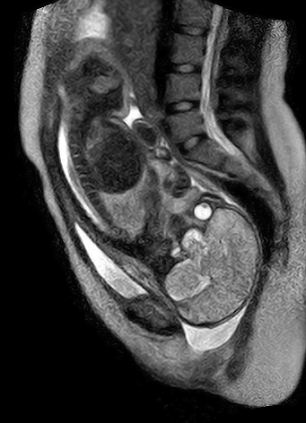

Επιστήμονες σε νοσοκομείο του Βερολίνου έβγαλαν τις πρώτες εικόνες με μαγνητικό τομογράφο κατά την διαδικασία της γέννας.

Η μητέρα γέννησε μέσα στον μαγνητικό τομογράφο που είχε διαμορφωθεί ειδικά για την περίσταση.

Τα αποτελέσματα αυτού του εγχειρήματος είναι πολύ σημαντικά γιατί μπορούν να πάρουν πολλές πληροφορίες που δεν είχαν πριν για την κατάσταση του μωρού κατά τη διαδικασία της γέννησης.

Το μόνο μειονέκτημα του μαγνητικού τομογράφου είναι ότι κάνει πάρα πολύ θόρυβο. Κατά την διάρκεια της διαδικασίας η μητέρα φορούσε ωτοασπίδες και με το που άνοιξε ο αμνιακός σάκος έκλεισαν τον μαγνητικό τομογράφο για να μην βλάψουν την ακοή του παιδιού.